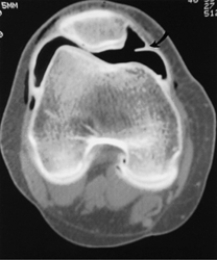

Q10: If an individual has a meniscus tear,